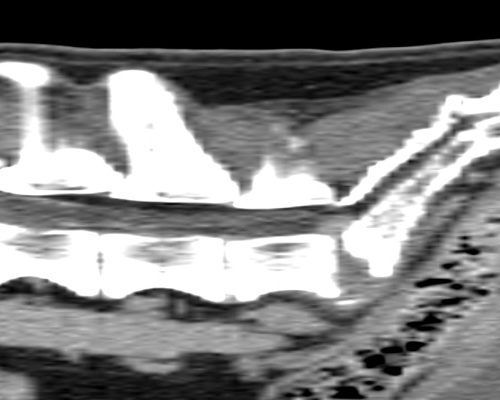

TC MULTISTRATO